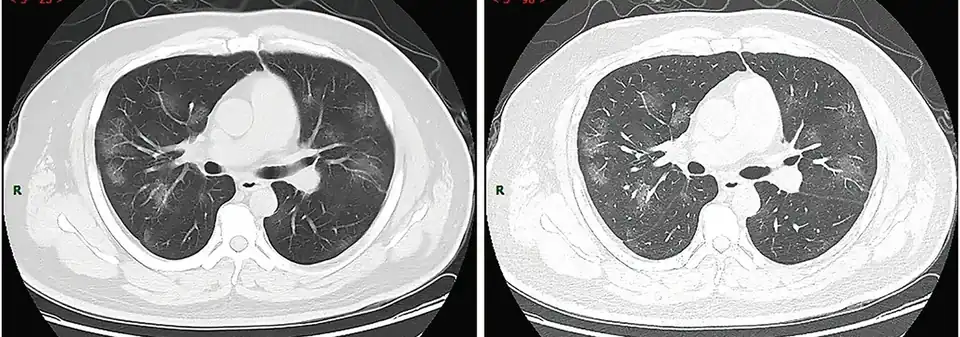

Radiologische tests

Met beeldvormend medisch onderzoek van de borstkas kunnen longafwijkingen gezien worden die mogelijk verband houden met COVID-19.

In een literatuuronderzoek van maart 2020 werd geconcludeerd dat "thoraxfoto's van de borstkas in een vroeg stadium van weinig diagnostische waarde zijn, terwijl CT-scans mogelijk al voor het begin van de symptomen het virus kunnen detecteren."[31][32]

Een studie waarin PCR wordt vergeleken met CT in Wuhan in het epicentrum van de huidige pandemie, heeft gesuggereerd dat CT significant gevoeliger is dan PCR, hoewel minder specifiek.[33]

Diagnose op grond van CT-scans is door zijn snelheid een goed alternatief voor PCR-test en heeft bovendien als voordeel dat ook de ernst van de ziekte in de longen is vast te stellen.[34]

Visuele analyse

Een kleinschalige studie toonde aan dat Chinese radiologen 72-94% gevoeligheid en 24-94% specificiteit toonden bij het differentiëren van COVID-19 van andere soorten virale longontsteking met behulp van CT-beeldvorming.[36]

Computeranalyse

Met behulp van kunstmatige intelligentie werd een hogere specificiteit bereikt.[37][38]

-

CT-scan van de borstkas van 38-jarige man met COVID-symptomen -

CT-scan van 50-jarige vrouw met COVID-symptomen